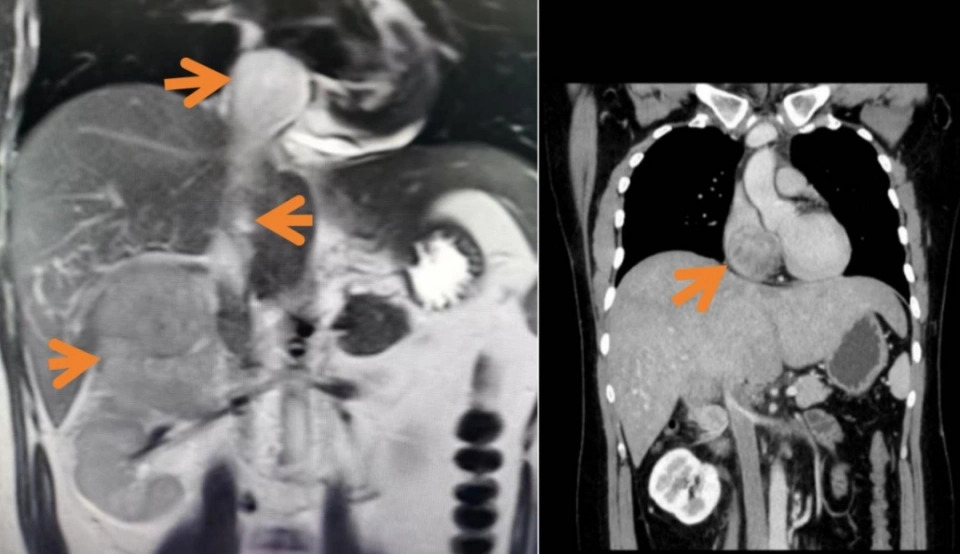

Hình ảnh khối u tuyến thượng thận 10cm, chèn ép tĩnh mạch của nhân vật (NV cung cấp)

Kết quả chụp CT phát hiện trong ổ bụng của anh xuất hiện một khối u lớn kèm huyết khối tĩnh mạch chủ dưới. Theo lời bác sĩ tại Bệnh viện Nhân dân số 1 Hàng Châu (Chiết Giang, Trung Quốc), đó là ung thư vỏ thượng thận phải. Kích thước lớn tới 10cm và vị trí sát gan và thận, đang chèn ép mạch máu quan trọng. Kèm theo đó là một khối huyết khối lan đến tĩnh mạch chủ dưới và tâm nhĩ phải. Tình trạng này không chỉ đe dọa tính mạng mà còn đặc biệt hiếm gặp, nhất là ở người trẻ tuổi.